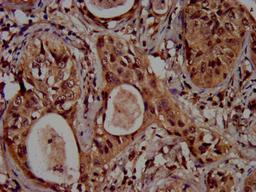

IHC image of CSB-PA010418OA04ncrHU diluted at 1:100 and staining in paraffin-embedded human cervical cancer performed on a Leica BondTM system. After dewaxing and hydration, antigen retrieval was mediated by high pressure in a citrate buffer (pH 6.0). Section was blocked with 10% normal goat serum 30min at RT. Then primary antibody (1% BSA) was incubated at 4°C overnight. The primary is detected by a biotinylated secondary antibody and visualized using an HRP conjugated SP system.